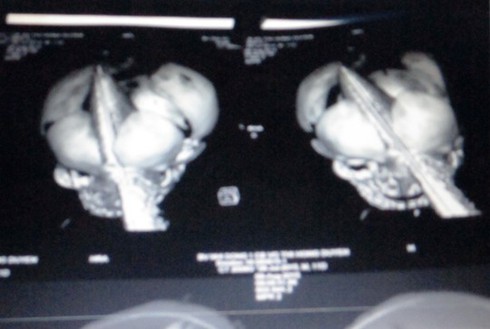

![]() |

Phim X-quang cho thấy vị trí lưỡi dao xuyên qua vùng sọ, mặt của cháu bé - ẢNH DO BV NHI ĐỒNG 1 CUNG CẤP |

Sau gần 3 giờ phẫu thuật, ê-kíp gồm các bác sĩ nhiều chuyên khoa của Bệnh viện Nhi Đồng 1 và bác sĩ khoa Ngoại thần kinh của Bệnh viện Nhân dân 115 đã lấy ra con dao với phần lưỡi dài trên 11 cm nằm trọn trong vùng đầu, mặt em bé. Rất may mắ, dù dao đâm ở rất gần vị trí mắt nhưng nhãn cầu cháu bé vẫn an toàn.